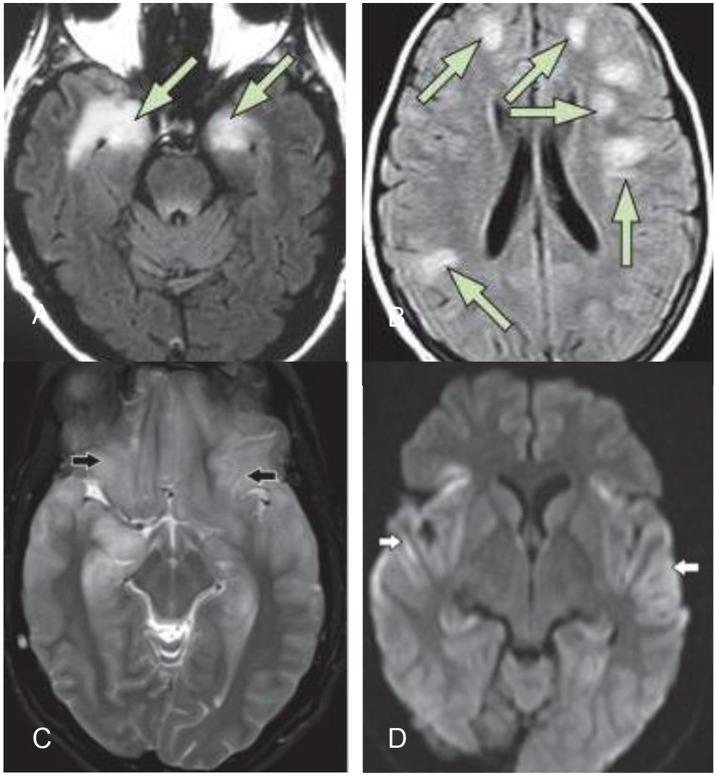

In recent years, new antibodies have been discovered which mediate autoimmune encephalitis. This immunological response can be triggered by an infection or a tumor. Classical onconeuronal antibodies are directed against intracellular neuronal agents but recently, a novel group of antibodies to neuronal cell-surface and synaptic antigens associated with different CNS-syndromes, has been discovered. Interestingly, the syndromes in this group can be successfully treated with immunotherapy and frequently do not have underlying tumors. The aim of this review is to describe the current state of knowledge about autoimmune encephalitis, in order to provide clinicians with a concise, up-to-date overview. Thus, a comprehensive literature search was performed in medical databases. The literature was carefully studied and new findings focusing on the symptoms, diagnosis and treatment were summarized and interpreted. Even though it might be challenging in some cases, the awareness of certain symptom constellations and demographic information, in combination with laboratory- and MRI-results, allows clinicians to make the diagnosis of probable autoimmune encephalitis at an early stage. Treatment can therefore be initiated faster, which significantly improves the outcome. Further investigations could define the underlying pathogenic mechanisms. Randomized controlled trials, paired with increasing clinical experience, will be necessary to improve the identification of affected patients, treatment strategies, and outcomes in the years to come.

近年来,已发现介导自身免疫性脑炎的新抗体。这种免疫反应可由感染或肿瘤引发。经典的肿瘤神经元抗体针对细胞内神经元成分,但最近发现了一组与不同中枢神经系统综合征相关的针对神经元细胞表面和突触抗原的新型抗体。有趣的是,该组综合征可用免疫疗法成功治疗,且通常没有潜在肿瘤。本综述的目的是描述自身免疫性脑炎的当前知识状态,以便为临床医生提供简洁、最新的概述。因此,在医学数据库中进行了全面的文献检索。对文献进行了仔细研究,并总结和解释了关注症状、诊断和治疗的新发现。尽管在某些情况下可能具有挑战性,但对某些症状组合和人口统计学信息的认识,结合实验室和磁共振成像结果,可使临床医生在早期做出可能的自身免疫性脑炎诊断。因此可以更快地开始治疗,这显著改善了预后。进一步的研究可以确定潜在的致病机制。在未来几年,随机对照试验以及不断增加的临床经验对于改善受影响患者的识别、治疗策略和预后将是必要的。